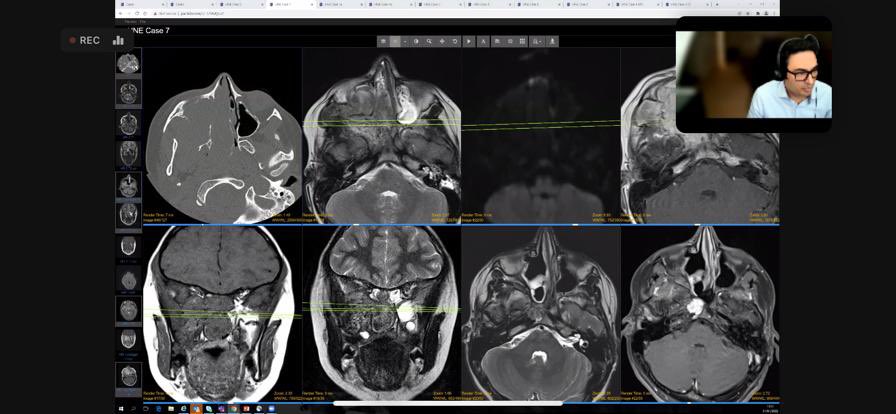

Wow! INCREDIBLE case-rich session from my amazing colleague @DrAtaSiddiqui top tips, practical pearls, exemplary live cases with audience participation using @pacsbin &interactive polls. Stellar job! 👏🏾👏🏾 @theBSNR @BSNRTrainees @BSHNI_UK @@ESNRad @ESHNRSociety @ASHNRSociety

Brilliant comprehensive run through of the tricky post operative spine by @RadheshLalam for @theBSNR educational program for our joint @BSSR_Site session 👏🏾👏🏾 @pacsbin integration and polls- great job!Missed it? Video coming soon 👉🏾 bsnr.org.uk/education/reco… #neurorad #foamrad